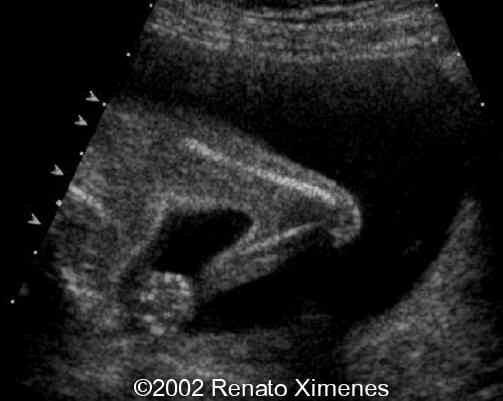

The critical image is the soft-tissue webbing of the rhizo-mesomelic joints. This is more than the simple contractures seen in many of the arthrogryposis.

case0072-7

case0072-8